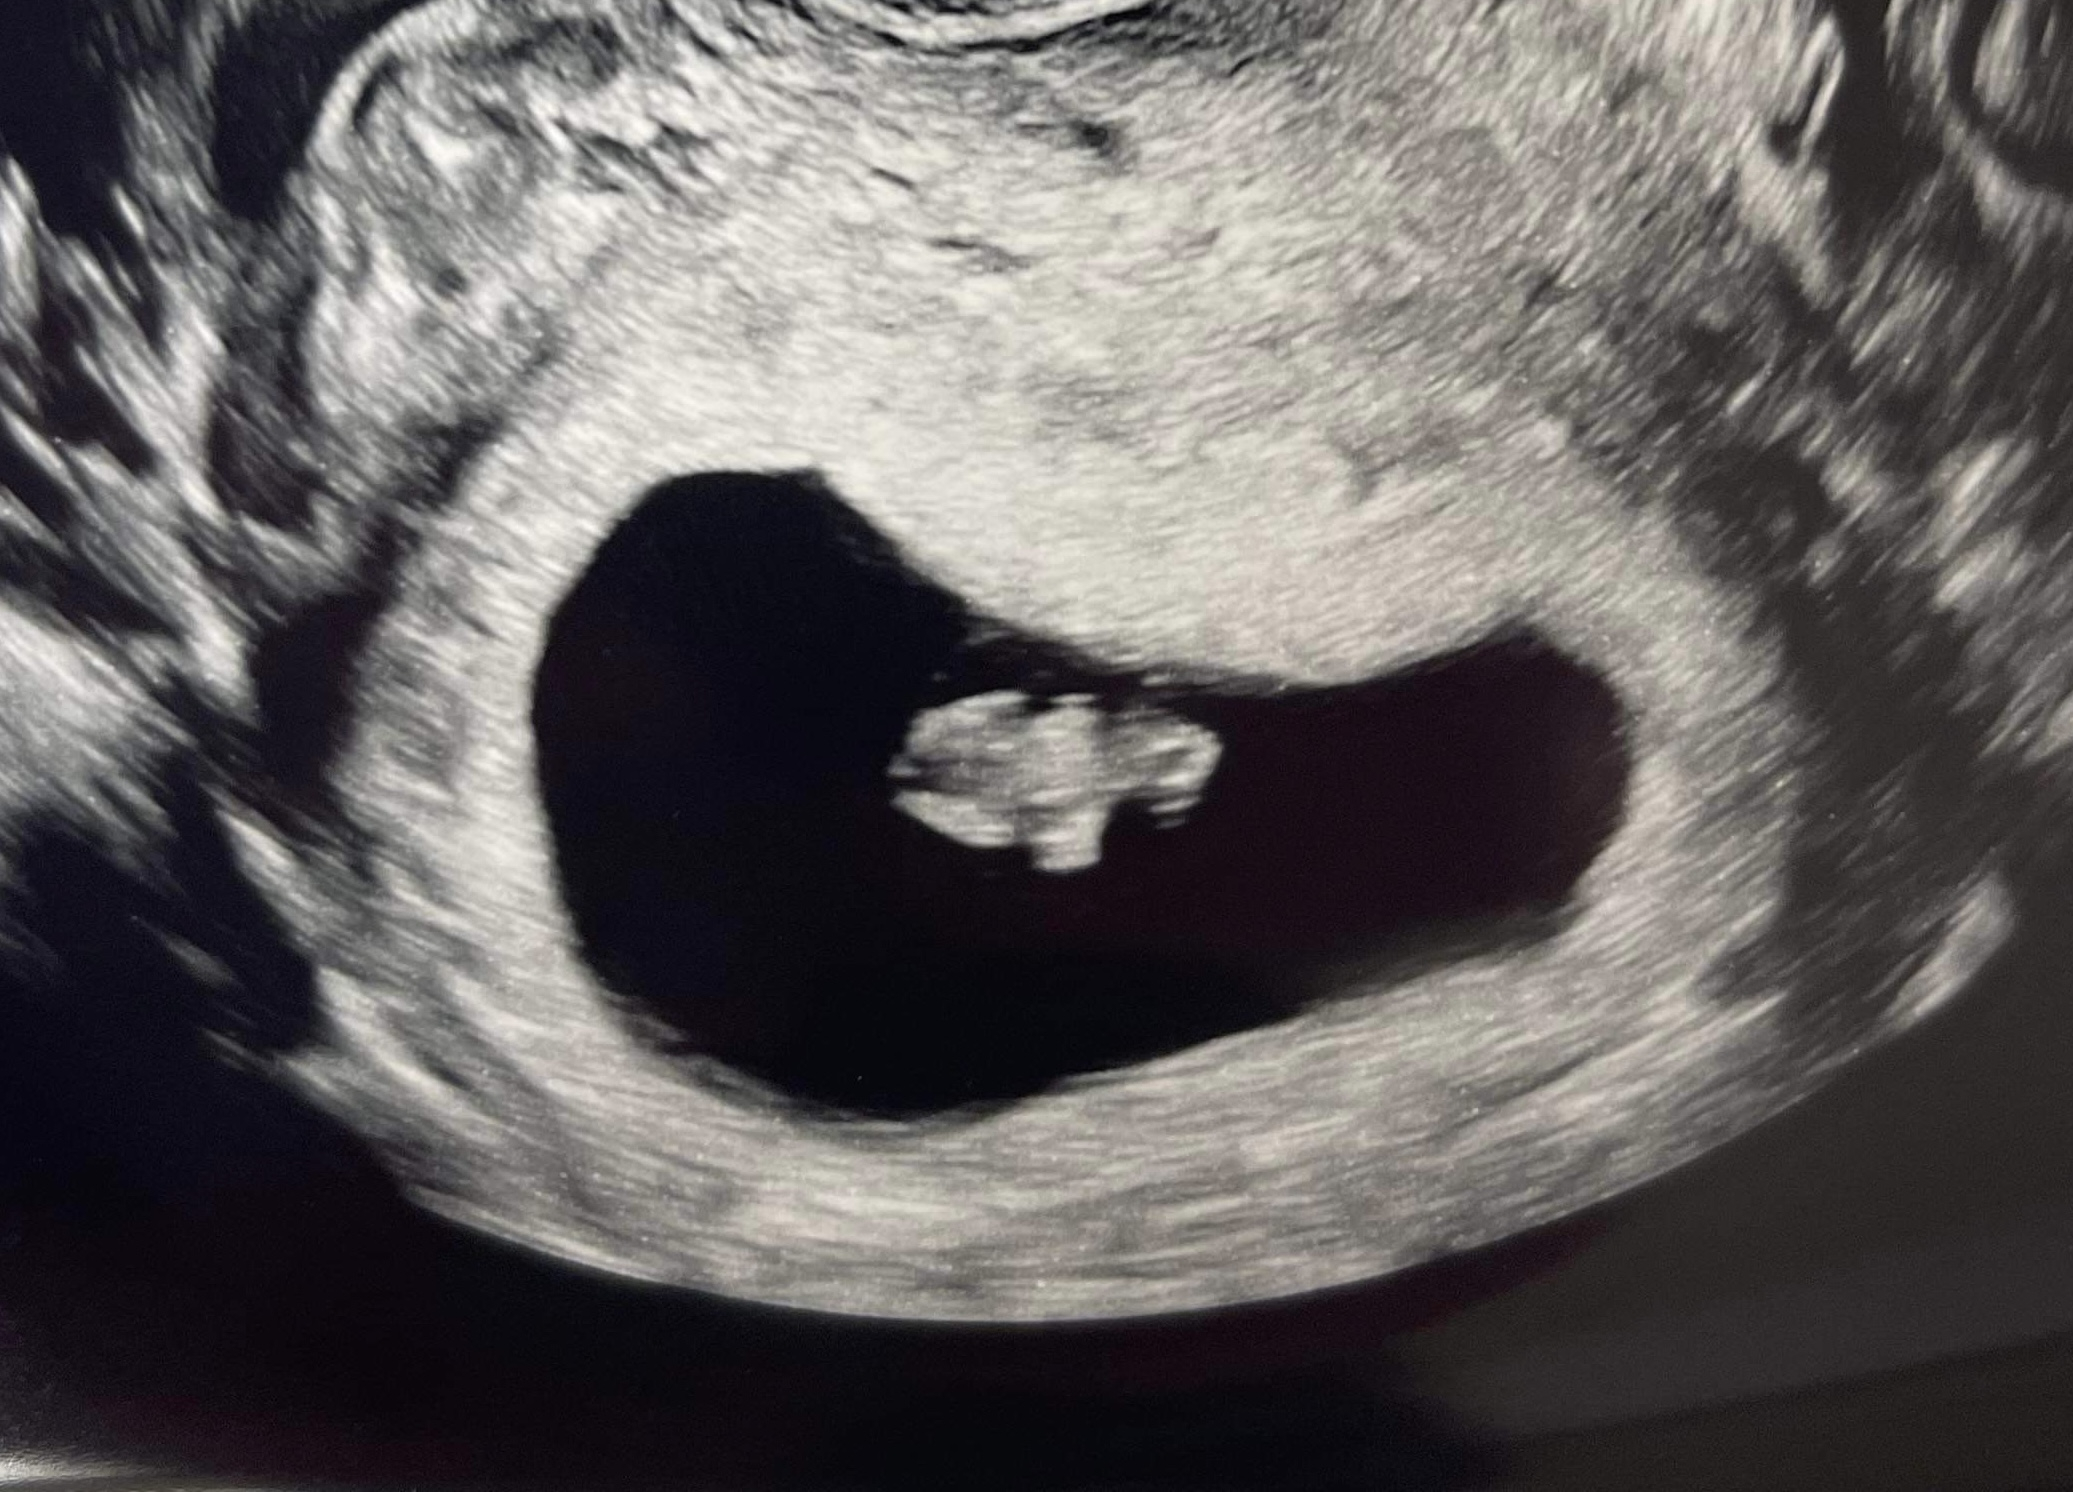

Got to see our little baby today! Measuring right on track, 7 weeks 1 day, and saw a beautiful little heartbeat of 144bpm! ❤️ I’m so relieved, we still have weeks to go to be out of the first trimester, but we never got to see the heartbeat with our previous loss.